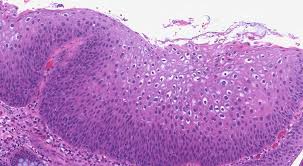

상피내암의 진단은 일반적으로 조직검사에 의해 이루어지며, 이를 통해 세포의 비정상성을 확인합니다. 자궁경부의 경우, 팝 스미어 검사(세포진 검사)를 통해 조기 진단이 가능합니다. 대장내시경을 이용한 대장암 조기 발견에서도 상피내암이 진단될 수 있습니다.

상피내암은 그 발생 위치에 따라 여러 가지 종류로 나눌 수 있습니다. 대표적인 상피내암의 종류는 다음과 같습니다:

- 자궁경부 상피내암 (Cervical Carcinoma In Situ)

- 유방 상피내암 (Ductal Carcinoma In Situ)

- 대장 상피내암 (Colorectal Carcinoma In Situ)

- 피부 상피내암 (Squamous Cell Carcinoma In Situ)

각 종류의 상피내암은 발생 지점에 따라 특정 증상과 특징을 보입니다. 예를 들어, 자궁경부 상피내암의 경우, 초기에는 증상이 거의 없지만, 진행 시에는 비정상적인 출혈이나 통증 등의 증상이 나타날 수 있습니다. 이러한 증상들은 여성이 정기적으로 건강 검진을 받는 것이 얼마나 중요한지를 잘 보여줍니다.